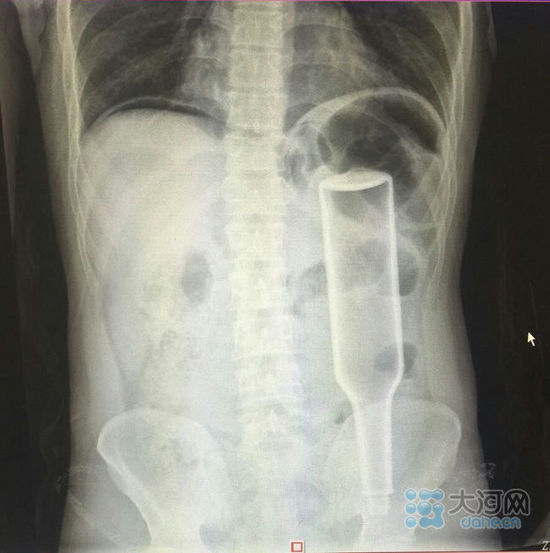

郑州男子晚上喝酒后本想抄近路回家,结果因为在路边小便后没提好裤子导致翻栅栏时迈不开腿,直接被卡在栅栏上,肚子被栅栏顶的尖刺刺穿。多亏路人发现并及时拨打119报警才被成功解救。 前两天,晚上十点半左右

郑州男子晚上喝酒后本想抄近路回家,结果因为在路边小便后没提好裤子导致翻栅栏时迈不开腿,直接被卡在栅栏上,肚子被栅栏顶的尖刺刺穿。多亏路人发现并及时拨打119报警才被成功解救。

前两天,晚上十点半左右,在郑州市金水东路与黄河东路交叉口附近一小区门口,一名男子的肚子被戳透。

天哪!这是谁下的狠手?这事要从半个小时前说起,当时这名男子还没有躺在救护车上,而是趴在小区的栅栏上!肚子被栅栏顶上的尖刺刺穿!!现场十分危急。

男子浑身酒气,被困在栅栏上无法动弹,一直在痛苦的呻吟着,疼死了,疼死了!多亏路人发现,并及时拨打了119报警。

消防官兵赶到后,为防止二次受伤,一边用钢叉顶住男子上半身,一边用液压剪扩张器,对栅栏顶上尖刺根部进行剪切。

终于,20分钟后,这名男子被成功解救,送往医院救治。

可是好端端的怎么就趴到栅栏上了呢?原来,这名男子晚上喝了点酒,本想抄个近路回家,结果因为在路边小便后没有提好裤子,导致翻栅栏的时候迈不开腿,直接被卡在栅栏上面,肚子被栅栏顶上的尖刺当场刺穿。为了抄个近路,导致肚子被戳穿,这还真是不走寻常路啊!